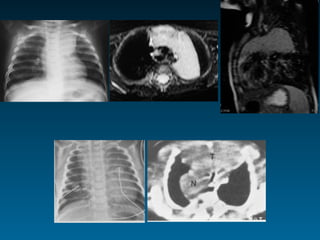

? πρόσθιο μεσοθωράκιο

Έφηβοι

8 μηνών, βρογχιολίτις

14 μηνών, Εμπύρετο προ 2μήνου, παθολογική α/α

θώρακος, επανέλεγχος

Θύμος

•     Διεύρυνση ανώτερου πρόσθιου

μεσοθωρακίου

•     Ευγενική τριγωνική δομή

•     Ακεραιότητα πνευμονικών δομών

•     Παιδιά έως 6 ετών

• Εναλλακτικά της α/ας ΥΧ       -ΥΤ-ΜΤ